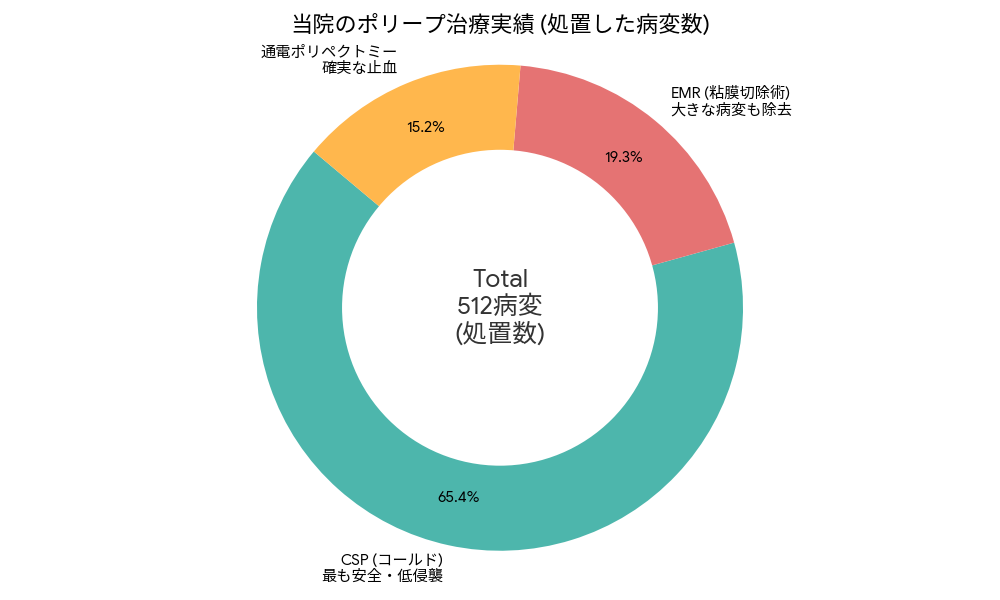

当院で実際に行った大腸ポリープ切除の実績と、安全への取り組みについてまとめています。